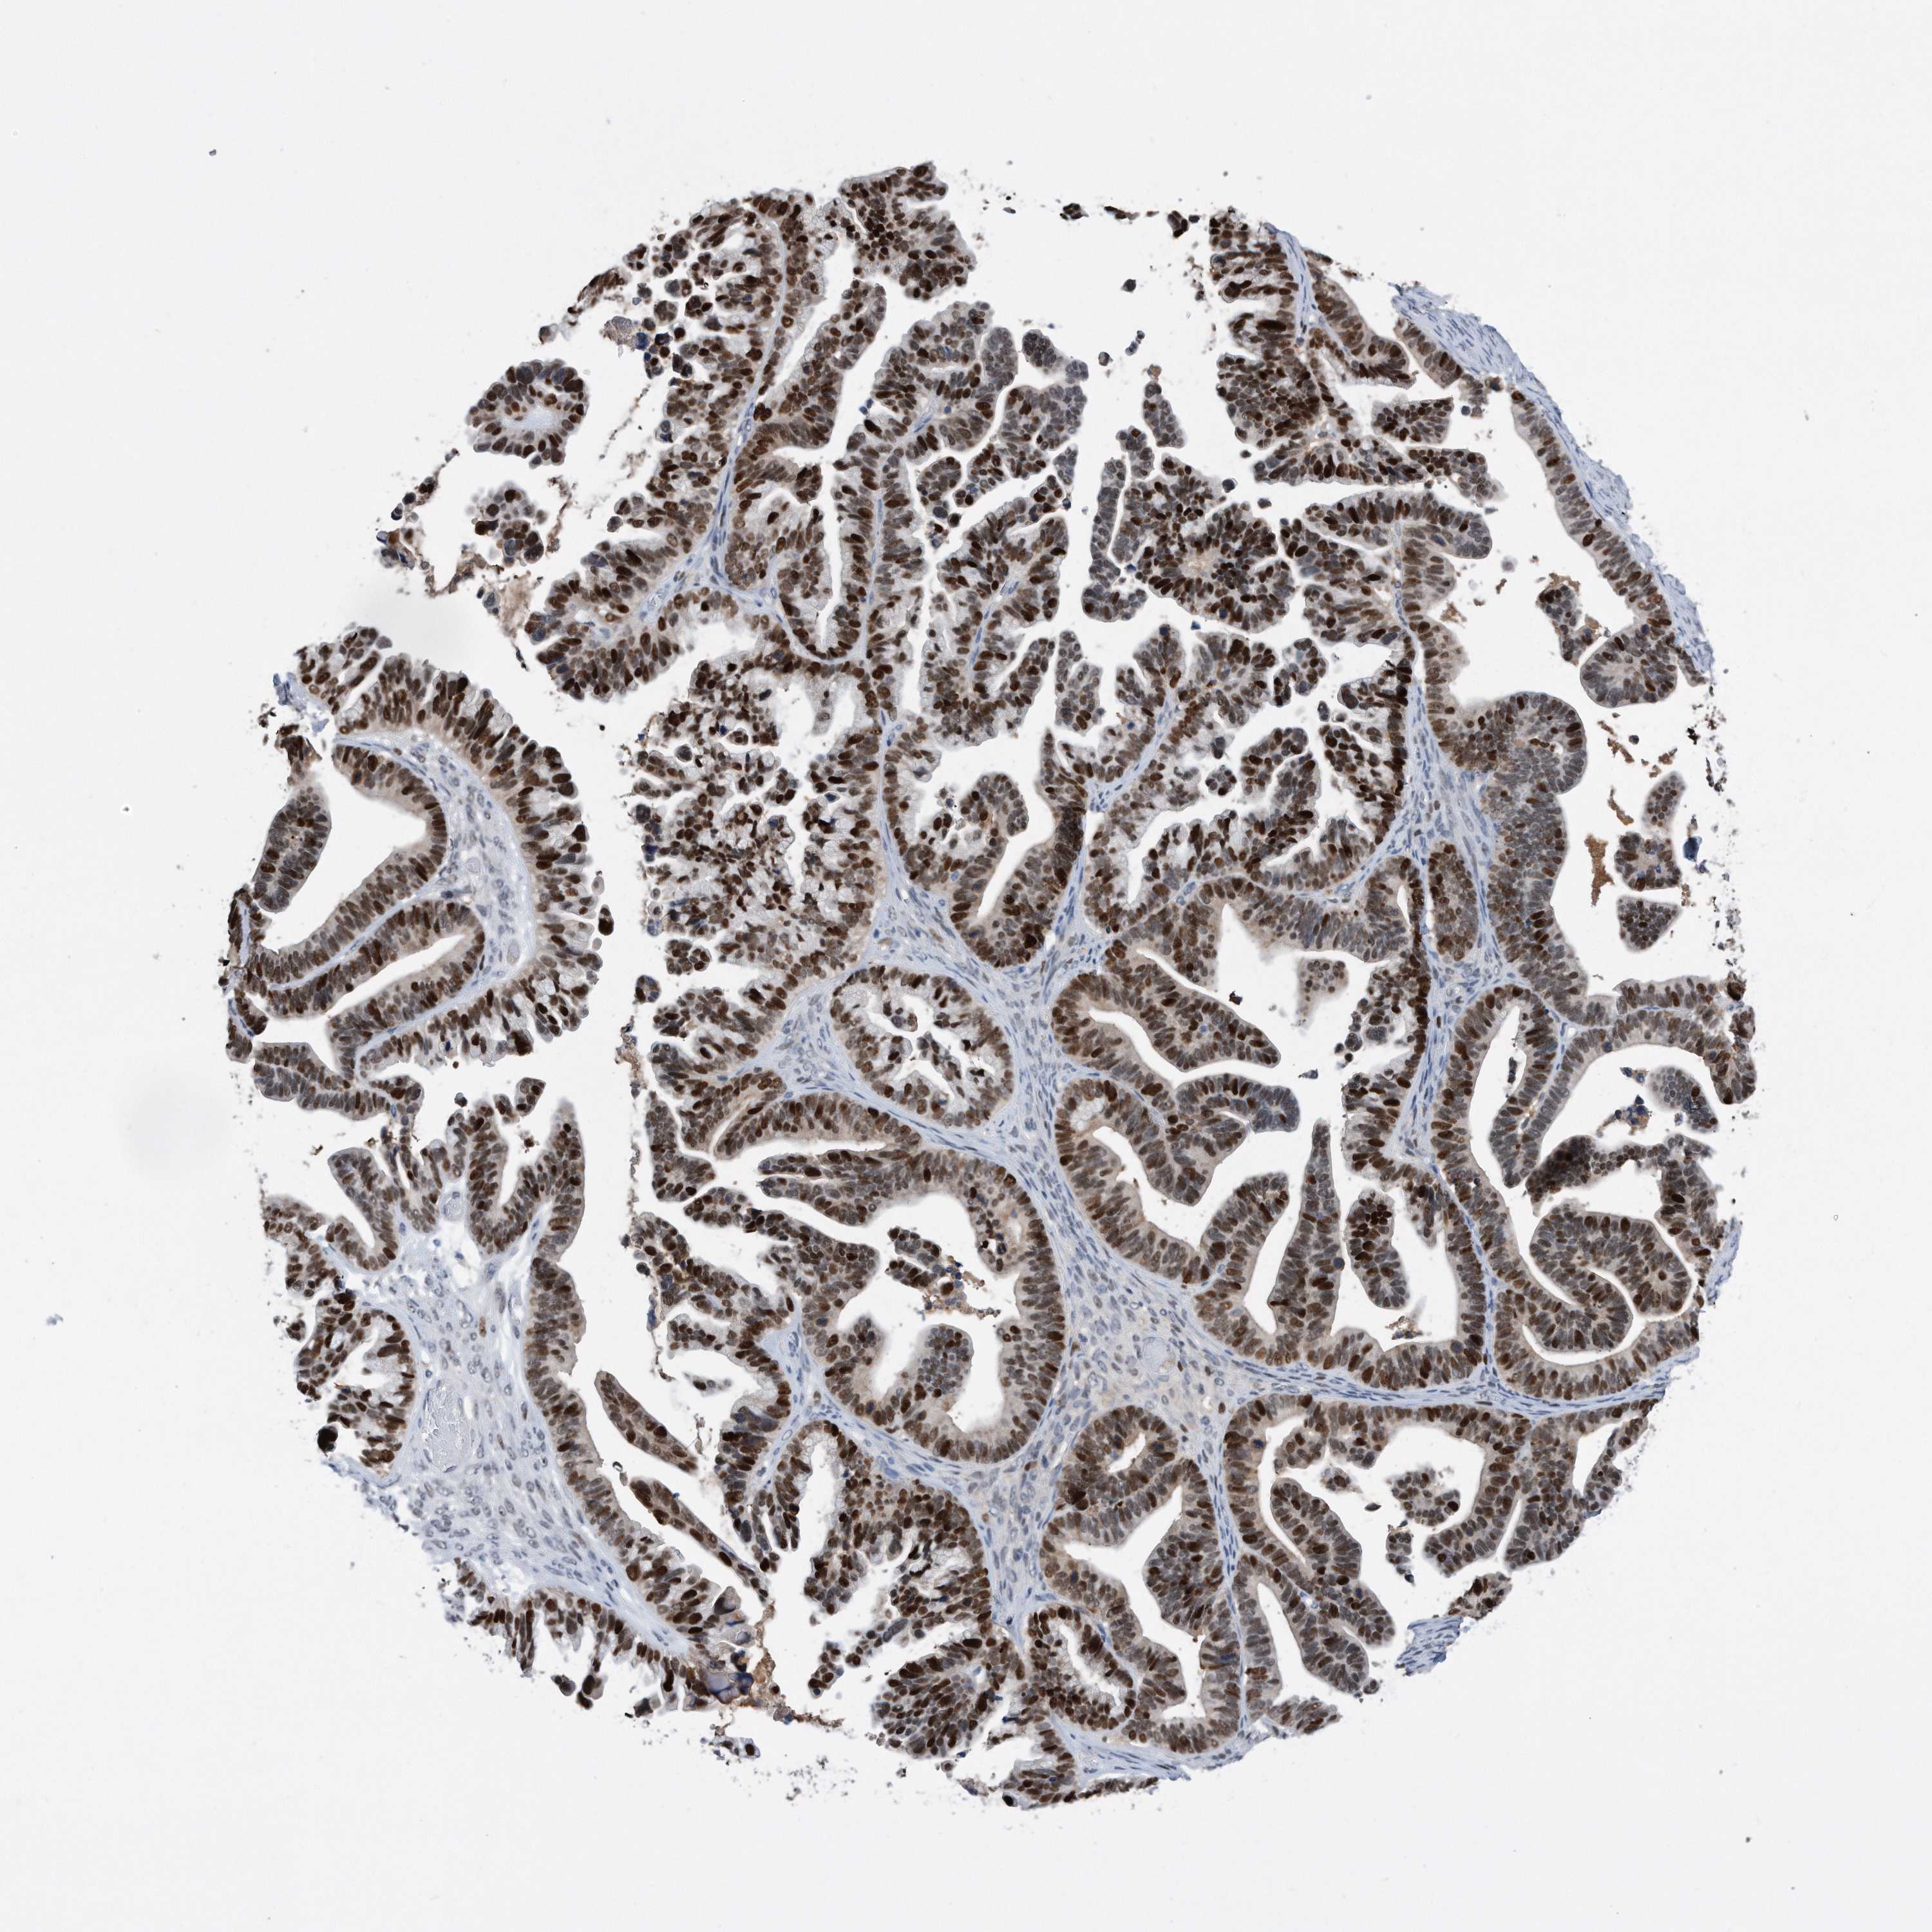

OVARIAN CANCER - Protein expressioni

A mouse-over function shows sample information and annotation data. Click on an image to view it in a full screen mode. Samples can be filtered based on level of antibody staining by selecting one or several of the following categories: high, medium, low and not detected. The assay and annotation is described here.

Note that samples used for immunohistochemistry by the Human Protein Atlas do not correspond to samples in the TCGA dataset.

Antibody stainingi

Antibody staining in the annotated cell types in the current human tissue is reported as not detected, low, medium, or high, based on conventional immunohistochemistry profiling in selected tissues. This score is based on the combination of the staining intensity and fraction of stained cells.

Each image is clickable and will lead to virtual microscopy that enables deeper exploration of all samples and also displays staining intensity scores, fraction scores and subcellular localization as well as patient and tissue information for each sample.

HPA030521

Cystadenocarcinoma, serous, NOS